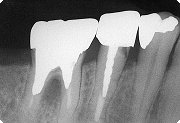

14

| 術前のX線写真。分岐部にややX線の透過性が認められる。 |

15

| 術後2年目のX線写真。術前と比較して分岐部の不透過性が増してきているように思われる。 |